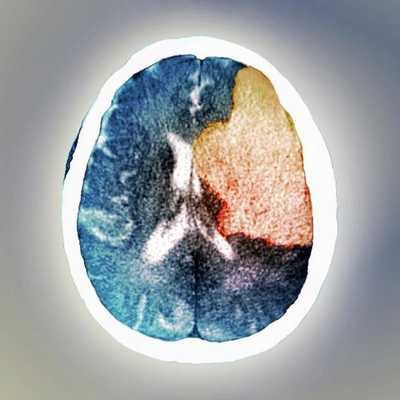

Постинсультный психоз — редкое явление, но его изучение внесло значительный вклад не только в понимание формирования бреда, но и галлюцинаций. Данные клинических исследований больных с очаговыми инсультами показывают, что бред развивается после одностороннего поражения правого полушария. Однако у большинства пациентов с правополушарным инсультом бред не развивается, и расширенный анализ нейровизуализации прояснил, почему этот симптом развивается лишь у небольшой части пациентов. Поражения правой латеральной префронтальной коры или поражения, связанные с этой областью, коррелируют с бредовыми убеждениями. Исследования больных первичным психозом, например шизофренией, или под влиянием психогенного препарата кетамина также проявляют аномальную функцию этой области по отношению к выраженности бреда.

Вывод этих исследований состоит в том, что правая латеральная префронтальная кора является своего рода "узлом" в нейронной сети, которая включает базальные ганглии и лимбическую систему и получает входные данные от дофаминовых нейронов среднего мозга. У пациентов с шизофренией или с риском развития психоза нарушена регуляция дофамина, и данные свидетельствуют о том, что ошибочная передача сигналов дофамина является предшественником формирования бреда, поэтому вполне вероятно, что механизм формирования бреда одинаков как при первичном, так и при вторичном психозе. Это согласуется с тем, что основой лечения обоих состояний являются антипсихотические препараты. Однако, антипсихотических препаратов у людей с цереброваскулярными заболеваниями следует избегать, если это вообще возможно. Это связано с тем, что эпидемиологические исследования показали, что применение нейролептиков связано с повышенным риском инсульта и, таким образом, усугубляет возможность дальнейшего нарушения мозгового кровообращения.

Из-за редкости постинсультного психоза и четких указаний на то, что он напрямую связан с повреждением правого полушария, в нескольких исследованиях искали признаки, которые отличают пациентов с бредом и без бреда. Исследователи проанализировали последовательные госпитализации пациентов с инсультом в стационарное отделение. Они обнаружили, что за 9-летний период только у 8 пациентов развились бредовые убеждения, и у всех были односторонние поражения правого полушария. После исключения пациентов с психозом в преморбидном анамнезе они сопоставили 5 оставшихся пациентов с 5 другими пациентами с инсультом без бреда, но со схожими демографическими характеристиками, локализацией и объемом поражения. Когда они оценили свои КТ-сканы головного мозга, единственное структурное различие между двумя группами заключалось в том, что у психотических пациентов была более выраженная подкорковая атрофия, о чем свидетельствовали более широкие третьи желудочки и передние рога боковых желудочков. Исследователи пришли к выводу, что существовавшая ранее подкорковая атрофия является фактором риска развития бреда после правополушарного инсульта. Напомню читателю, что патологическое вовлечение базальных ганглиев/лимбической системы является необходимым условием развития бреда. В том же духе другие исследователи оценили психическое состояние 360 пациентов, последовательно поступивших с инсультом, и обнаружили 15 случаев бреда. У всех были односторонние поражения правого полушария, и ни у кого не было интеркуррентной деменции или психоза в анамнезе. Важно отметить, что ни у одного из 170 пациентов с односторонним поражением левого полушария не развился бред. Изучение их сканов головного мозга показало, что преобладающим местом поражения у пациентов с бредом была задняя височно-теменная область, но, поскольку были другие с чисто таламическими поражениями, они не смогли определить, были ли общие характеристики поражения в этой группе. У большинства пациентов был бред преследования, но у 6 были так называемые содержательно-специфические бредовые идеи в форме синдромов ошибочной идентификации. Примеры синдромов ошибочной идентификации включают пациентов, считающих знакомых людей самозванцами (синдром Капгра), или что разные люди являются одним и тем же человеком (бред Фреголи), или даже что их органы тела распались (синдром Котара).

Результаты многих исследований подтверждают гипотезу Cummings о том, что содержание бреда отражает функцию основной поврежденной коры, а также гипотезу Coltheart , который утверждает, что для возникновения синдрома ошибочной идентификации необходимы две аномалии психологической обработки. Тем не менее открытие того, что аномальная связь с правой латеральной префронтальной корой является общей для всех типов бреда, независимо от их содержания, ставит вопрос о том, может ли одна эта аномалия быть достаточной для возникновения бреда. Ряд нейровизуализационных исследования специально выявили аномалии этой области коры при постинсультном бреде.

Анализ перекрывающихся поражений на снимках головного мозга пациента показал, что общей областью повреждения при бреде была правая нижняя лобная извилина и нижележащее белое вещество верхнего продольного пучка и лучистого венца.

Данные, изложенные выше, позволяют предположить, что когда бред развивается после очагового инсульта, правая префронтальная кора вовлекается в критический процесс либо из-за того, что она сама повреждена , либо из-за нарушения связи с другими поврежденными корковыми или подкорковыми областями.